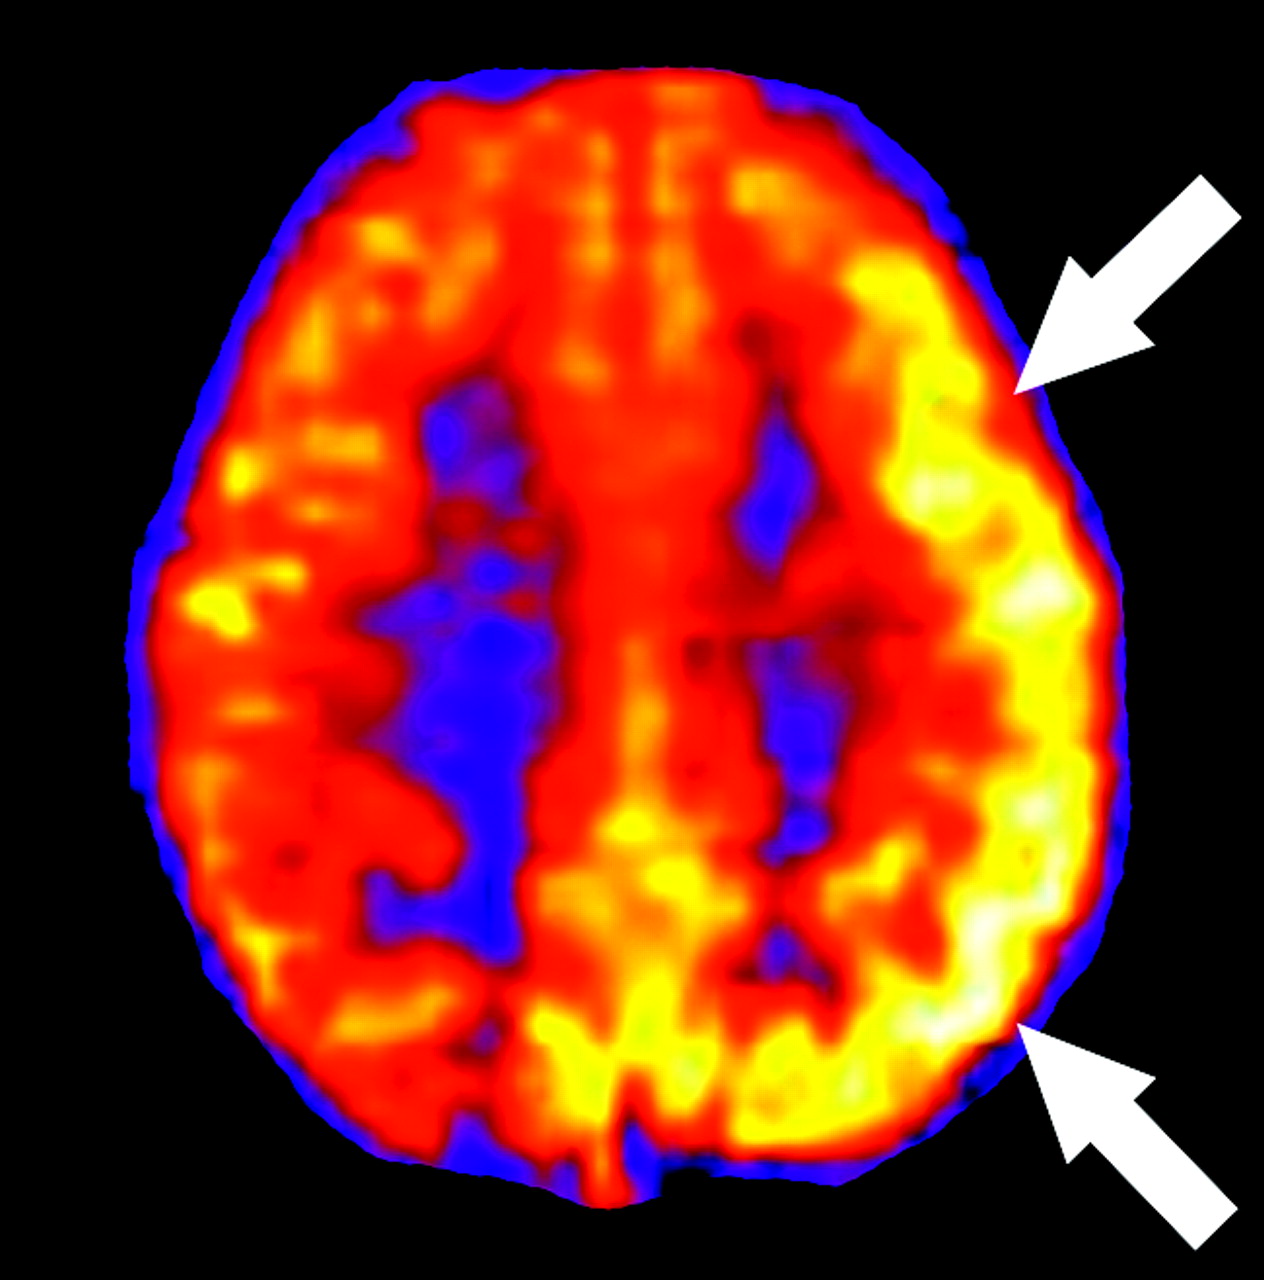

PRES and PRES-like syndromes can occur spontaneously or in association with uncontrolled hypertension, eclampsia, and cyclosporine toxicity and as a complication of certain chemotherapeutic regimens.14–16 A loss of autoregulatory control occurs in these syndromes, and initial attempts to maintain perfusion pressure result in arteriolar vasoconstriction. Hyperperfusion follows and results in reversible edema, more commonly in the vertebrobasilar vascular territories likely because of the relatively fewer perivascular sympathetic nerves in this area.14 Figure 11 demonstrates changes with time in a 31-year-old patient with PRES, including initial vasoconstriction and hypoperfusion followed by rebound hyperperfusion. ASL is a robust technique in the evaluation of hyperperfusion syndromes due to its repeatability and its strength in depicting high-flow states. Figure 12 demonstrates a case of post-endarterectomy hyperperfusion syndrome in a patient who had recently undergone ipsilateral carotid endarterectomy. This is a well-described phenomenon using other perfusion techniques17 and is presumed to result from loss of autoregulatory function.

Cerebral hyperperfusion after carotid endarterectomy (CEA). ASL CBF map obtained 2 days after left CEA for dizziness demonstrates markedly increased flow throughout the left hemisphere (arrows).